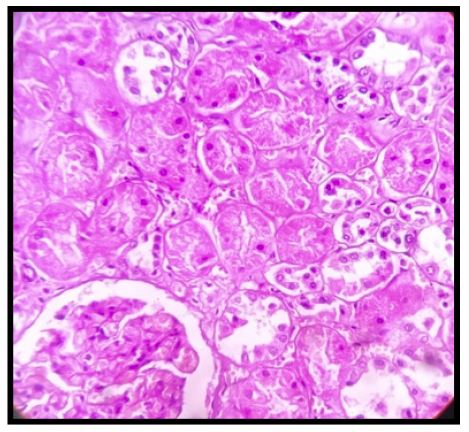

• Sections from both kidneys show tubular necrosis of mainly proximal convoluted tubules. Glomeruli are uninvolved (Figure 2).

Figure 2: Photomicrograph of proximal tubular necrosis with normal-looking glomerulus and distal tubules. (H&E stain, Mag 400x).

The predominant histologic finding of the kidney was tubular necrosis, which was direct evidence of Acute Kidney Injury (AKI). AKI is common amongst hospitalized patients with COVID-19 infection, which alone contributes to a major proportion of deaths [11]. Our current knowledge regarding the proposed mechanism for kidney injury by the coronavirus is limited [12,13], but a chronic kidney disease in the background could have played a supplemental role as was evidenced in our case. Thus, the plausible role of SARS-CoV-2 as a direct injurious agent in kidney pathology or secondary to aggressive fluid management and immunologic effect is yet to be explored [13].